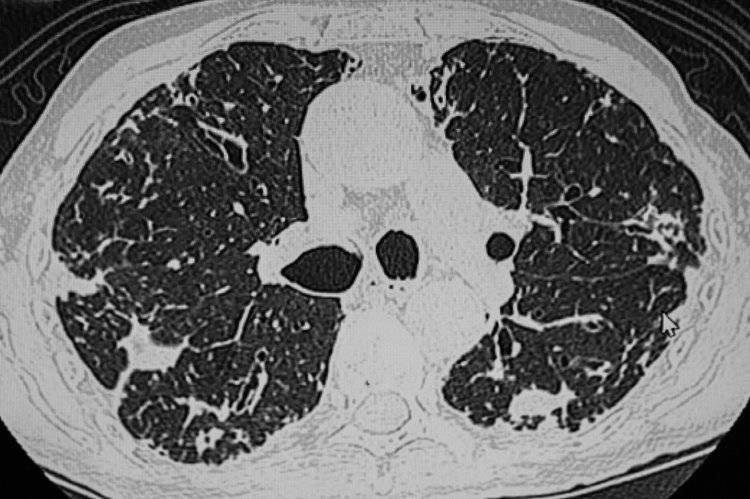

第二天就请假去了医院检查,结果发现结节已经增长到了14mm,且出现了实性成分。后续的增强CT、肿瘤标志物检查高度怀疑是恶性肿瘤,刘先生被安排入院进行相关治疗。好在刘先生的病程还处于早期,可以进行手术治疗,术后他很快就康复出院了。

很多患者在罹患肺结节后,身体没有任何不适症状,这种情况下只能通过胸部CT检查来发现结节。

三、肺结节就是肺癌?先别焦虑!

当胸部CT检查普遍后,很多人会被检查结果上的肺结节结果吓到,担心结节会发生癌变。在我国第31个全国肿瘤防治宣传周上,中国抗癌协会整合肿瘤分会青委会主委薛建新明确指出,体检中查出的肺结节95%为良性,只有5%有恶变的可能性。

有这几种特征的肺结节,恶性程度很高,要多加警惕:

• 大小:体积越大的结节危险程度就越高

• 数量:相同性质的结节,数量越多的恶性程度会比数量少的要高

• 长相:结节有毛刺征、分叶状、血管集束征、胸膜凹陷征等特征,恶性程度较高

• 位置:处于肺叶处的结节风险性较高,中下肺叶的则危险程度较低

• 变化:在发现结节后,医生会建议定期进行复查,复查过程中发现结节变大或是形态发生了改变,都要警惕可能是恶变了

• 密度:从危险程度上来看,是混合型>磨玻璃>实性